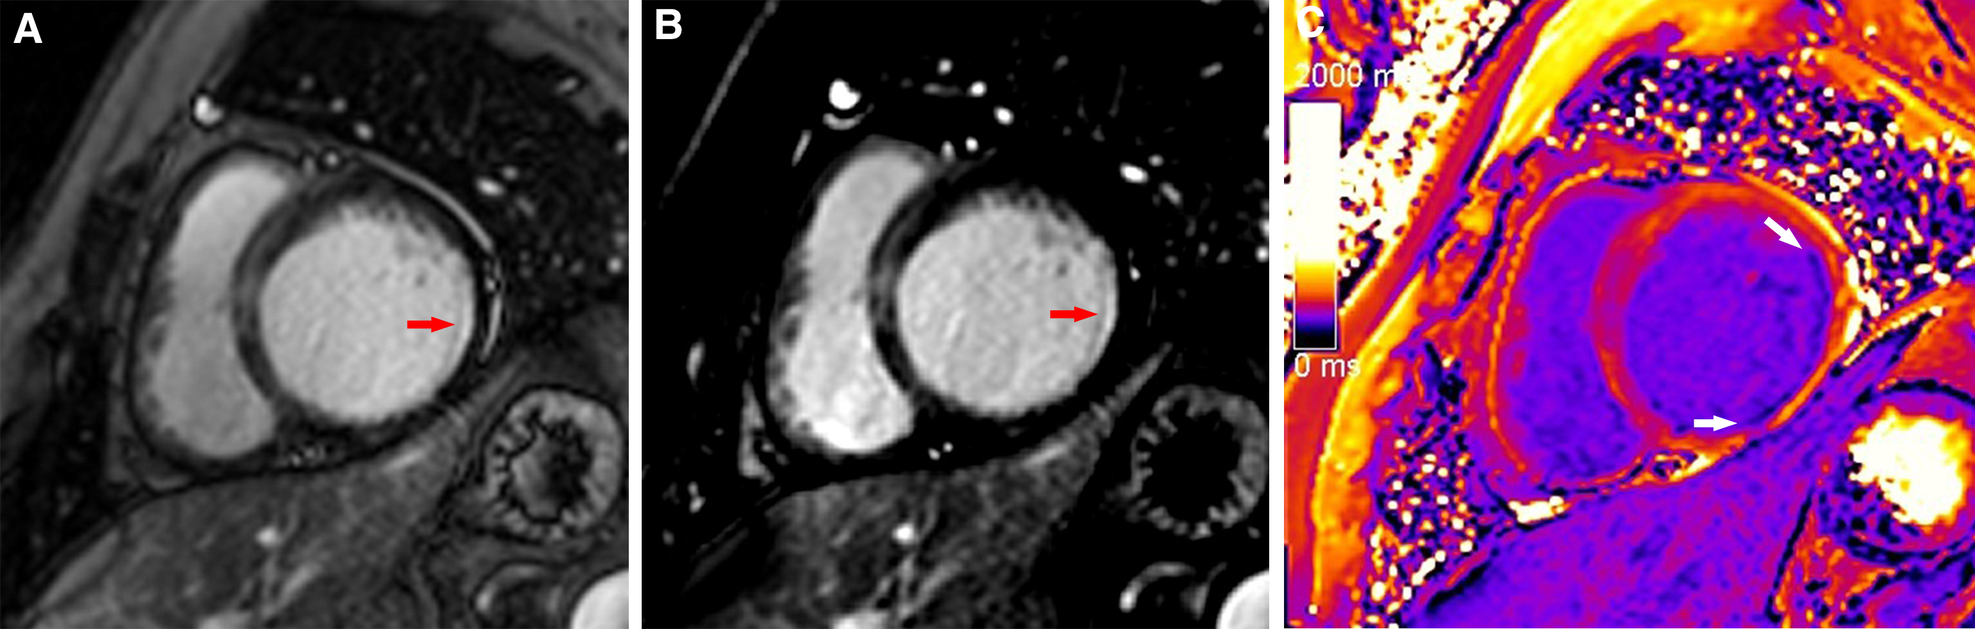

Figure 3

A typical case in which post-contrast T1 mapping improved the detection of subendocardial scarring. A subendocardial scar (red arrow) could be observed on magnitude (A) and PSIR (B) in the lateral wall of the base. The scar visibility was poor because it was adjacent to bright blood, making it challenging to evaluate the extent of subendocardial scarring. Greater extent of subendocardial scarring (white arrows) could be observed on post-contrast T1 mapping (C).